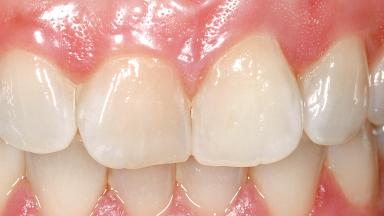

A 29-year-old female patient presented for treatment to replace the upper left central incisor tooth with an implant- supported restoration. The tooth had been intermittently symptomatic for the previous 12 months. The tooth had originally suffered trauma about 15 years previously. Several endodontic treatments had been performed, including an apicectomy procedure to retain the tooth. The patient was healthy and a non-smoker. She had reasonable expectations in regard to esthetic outcomes and the risk of marginal tissue recession following treatment. At medium smile, the gingival margins of the upper teeth were visible, with a display of 3 to 4 mm of the gingival margins. Gingival recession of tooth 21 and a discrepancy in the gingival levels between teeth 11 and 21 was observable during normal speech and smile.

| Soft Tissue Contour and Volume | Slightly compromised |